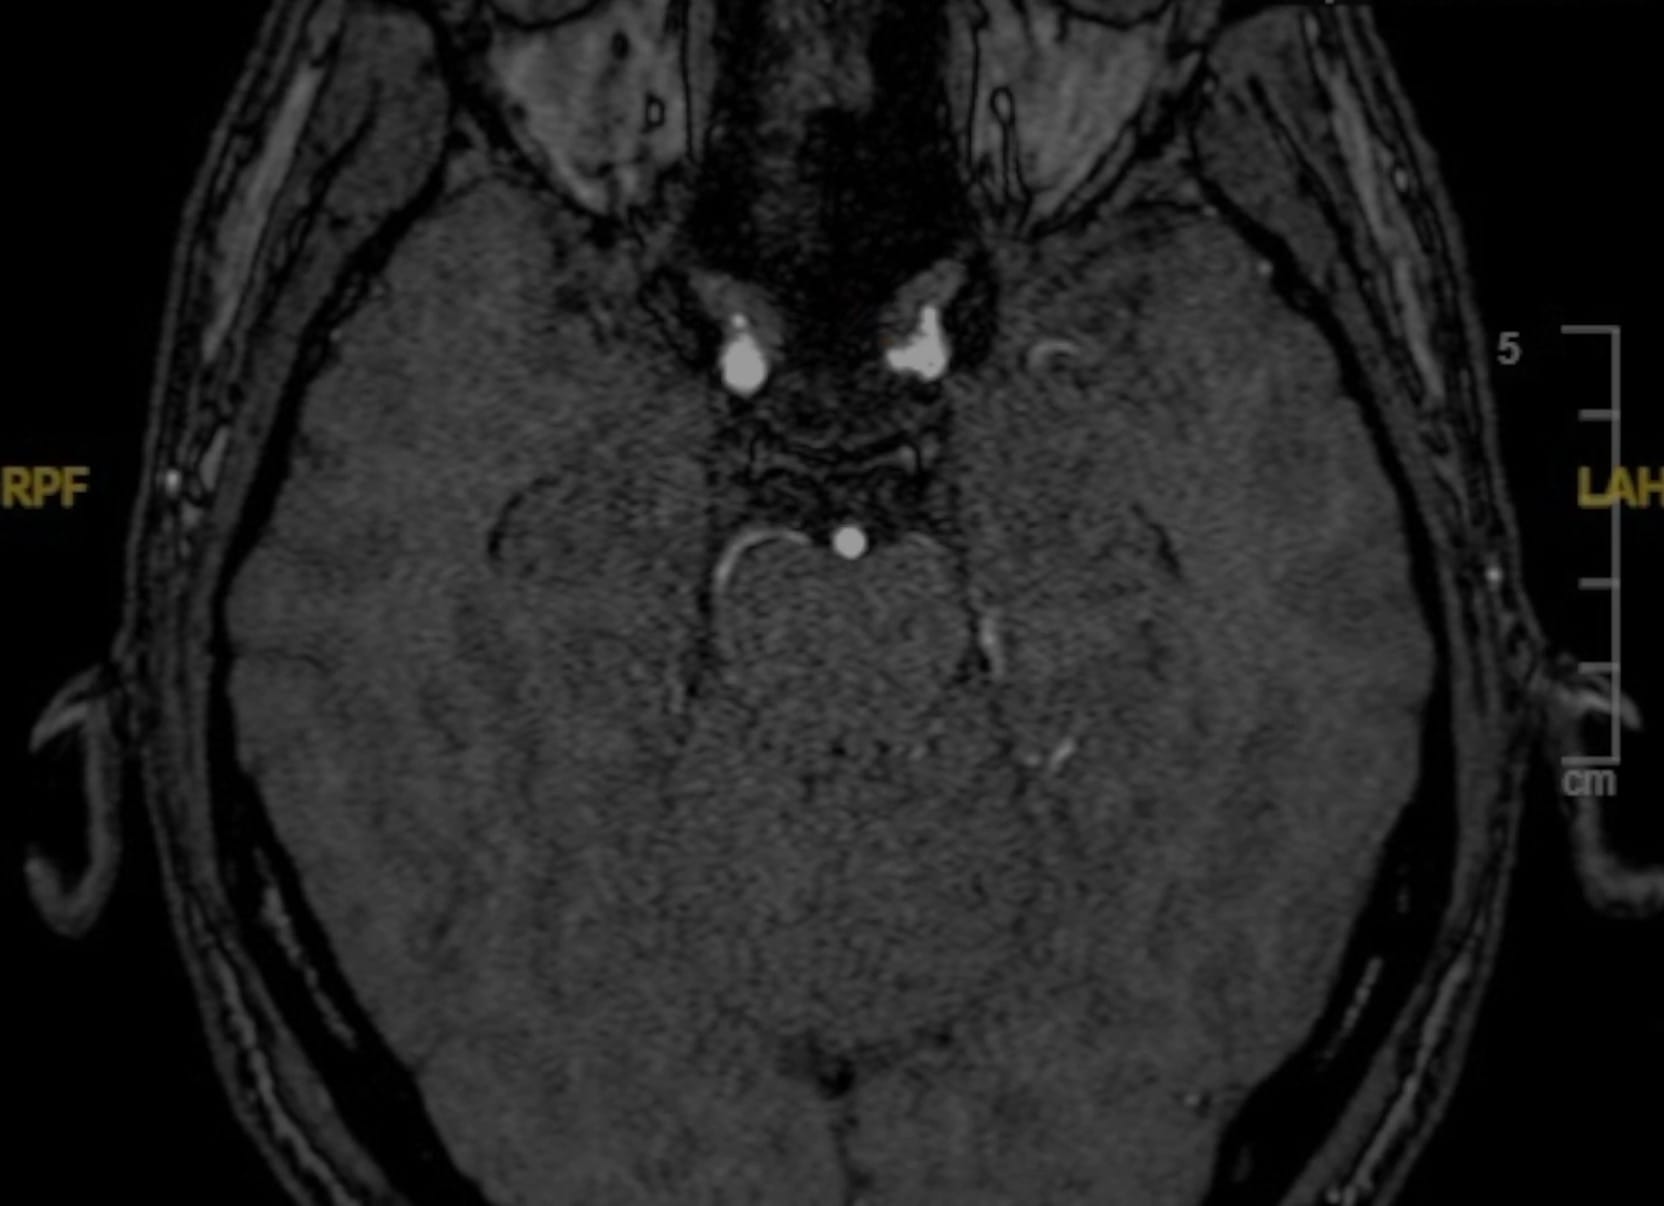

El paciente, de 33 años, fue diagnosticado de un aneurisma cerebral tras una cefalea intensa sin evidencia de sangrado subaracnoideo. Debido a los antecedentes familiares de hemorragia aneurismática y la preferencia explícita del paciente, se decidió optar por tratamiento quirúrgico.

El aneurisma aparece con un cuello bien definido.

Finalmente, la angiografía de control confirma un resultado satisfactorio sin complicaciones.